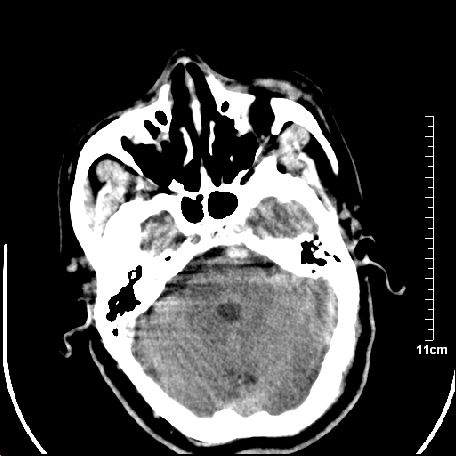

外伤患者,什么病,

外伤患者,没什么症状,

双侧外侧裂,左侧脑沟见高密度结节影,边清,还有鞍上池层面密度也高

1.左额叶脑软化灶。

2.老年脑,基底动脉硬化迂曲。

基底动脉硬化迂曲。高血红蛋白血症。